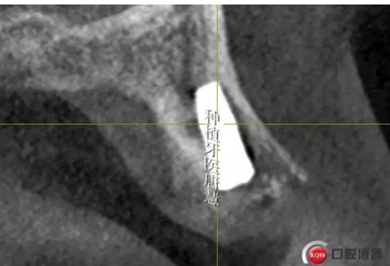

頰側(cè)骨皮質(zhì)缺失

16牙槽骨條件尚好

咬合間隙約3mm